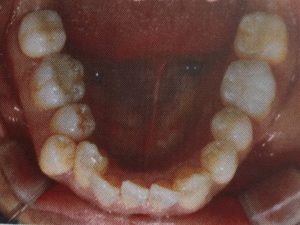

【下あご】

<矯正前 2018/06/30>

<フルリンガル装着時 2018/08/31>

<1回目調整後 2018/10/05>

<矯正インプラント装着時 2018/11/03>

※抜歯後のすき間が埋まりませんが、アーチはまずまずイメージ出来る感じになりました。